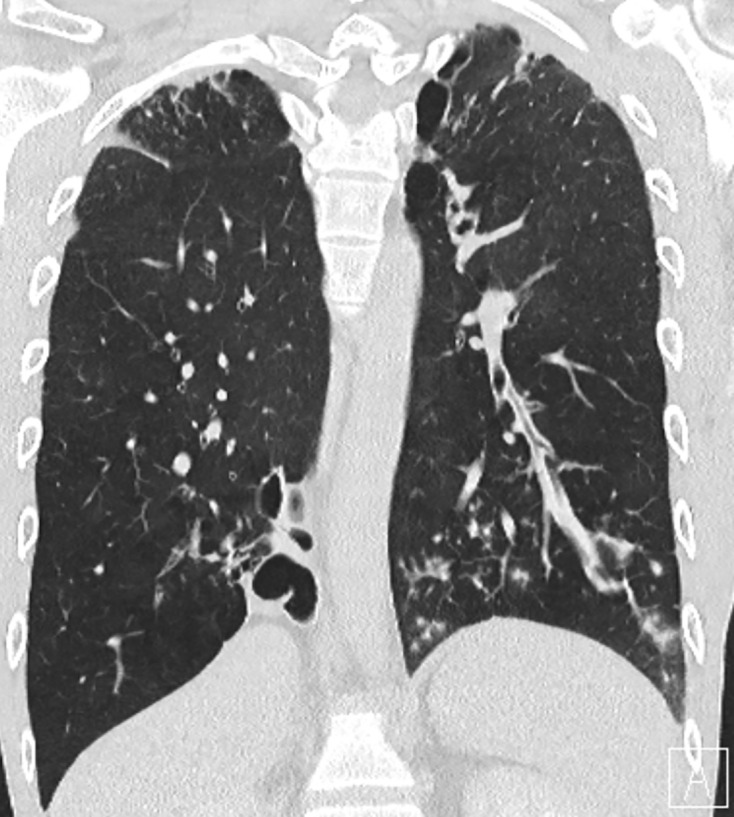

Background: Pulmonary sequestration is a congenital malformation in which nonfunctional lung tissue develops without connection to the bronchial system. The main complication is the occurrence of recurrent pneumonia.

Case presentation: We describe the case of a patient who was incidentally diagnosed with PS as part of the diagnostic algorithm for community-acquired pneumonia. Due to the relatively late diagnosis, the recurrent bronchopulmonary was conducive to the development of COPD and pulmonary emphysema. For prognostic reasons, surgical resection was performed by posterolateral thoracotomy.